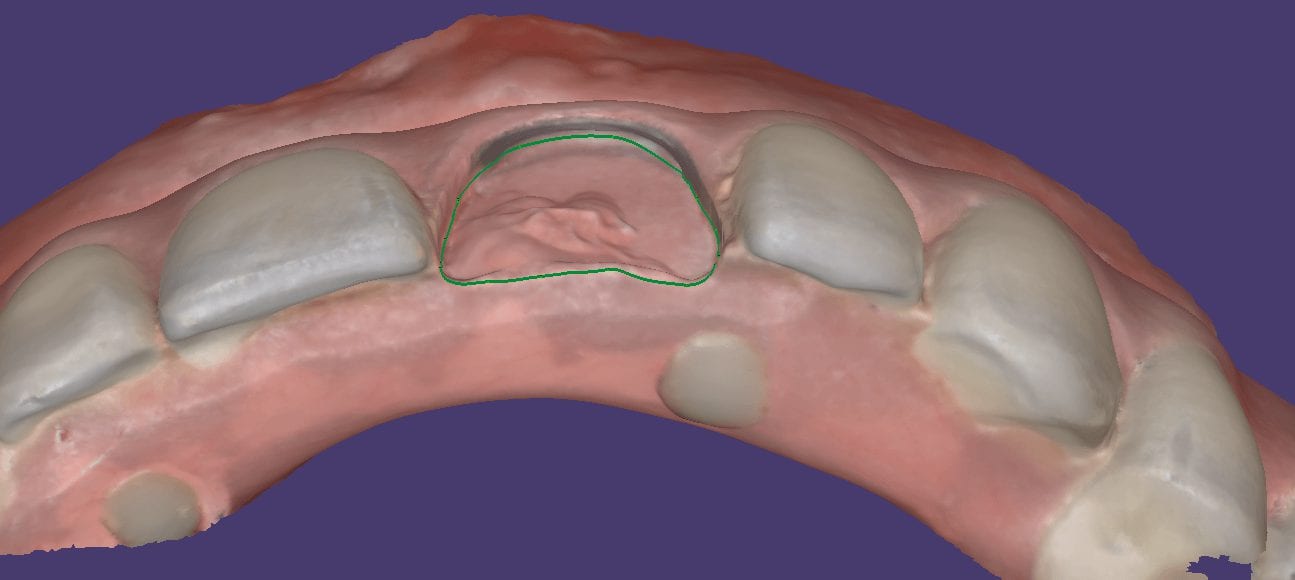

June 25, 2019This case shows the amount of control one can have over the fit of a restoration. The upper right first molar was imaged with the Medit i500 and then imported […]